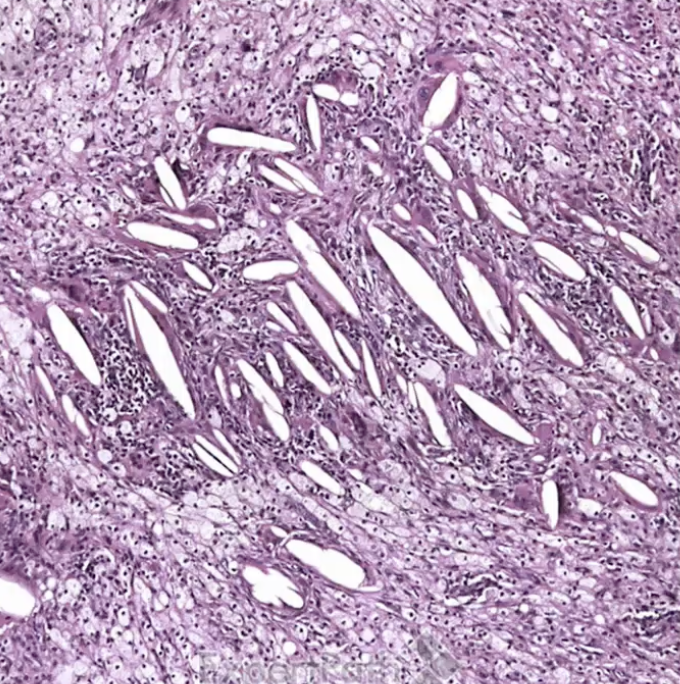

Cholesterolosis

Cholesterolosis